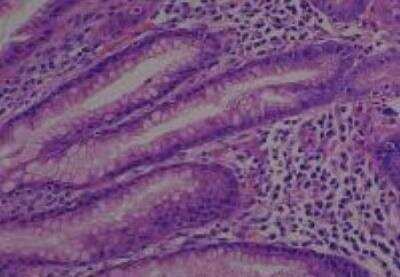

Hematoxylin & Eosin Stain: Human Common Tissue MicroArray (Normal Adjacent) [NBP2-30215] - 102. Stomach